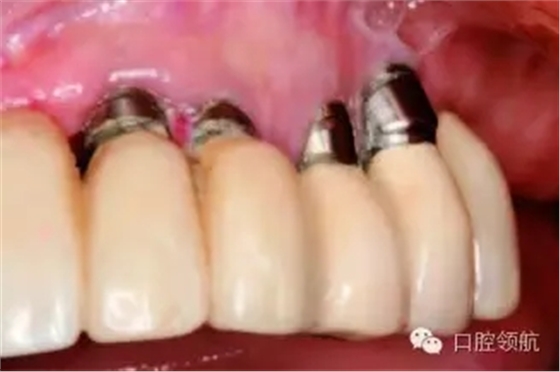

種植體植入深度不足,周圍沒有足夠的牙齦組織,就會導(dǎo)致金屬的暴露,從而產(chǎn)生美學(xué)問題(圖9.32)。另外,沒有操作空間,種植體到修復(fù)體的過渡就顯得很生硬。需要做蓋嵴,或?qū)⑿迯?fù)體做成蘑菇樣。這容易引起頸部食物滯留,使患者難以保持口腔衛(wèi)生(圖9.33a,b)。

圖9.32 種植體冠方牙齦萎縮,金屬暴露。

圖9.33 (a)患者很難自行清潔具有唇側(cè)蓋嵴的修復(fù)體。(b)種植體周圍炎癥會導(dǎo)致種植體失敗或取出。